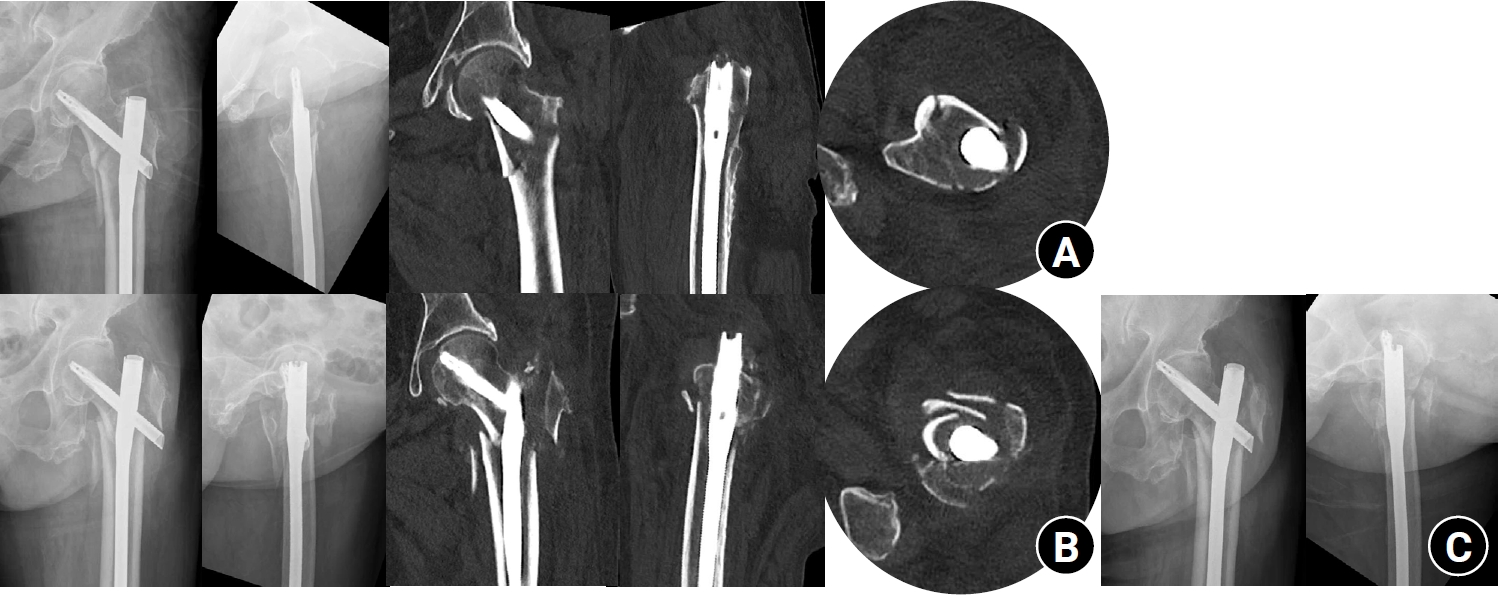

We retrospectively reviewed patients treated by a single surgeon in Korea between March 2022 and December 2024. Inclusion criteria were AO/OTA A1–A3 fractures, application of the leverage technique, preoperative and postoperative CT scans, and at least 6 months of follow-up. AMCS was assessed on CT as anterior support on axial images and medial support on coronal images, each graded as positive, neutral, or negative. Outcomes included time to union, union rate, change in neck-shaft angle, and treatment failure. Risk factors for failure were explored.

Of 273 patients screened, 53 met inclusion criteria. Follow-up was at least 6 months in all cases. Positive anterior support was achieved in 37 patients (69.8%) and positive medial support in 42 (79.2%). No patient demonstrated negative anterior support; one (1.9%) had negative medial support. Cortical support improved significantly after surgery (anterior P=0.026; medial P=0.001). Union occurred in 50 patients (96.2%) at 3.93±1.48 months. Mean varus change in neck-shaft angle at final follow-up was 1.75°±2.34°. Treatment failure occurred in three patients (5.7%). Anteromedial cortical breakage during follow-up differed between failure and non-failure groups (P=0.002), but regression identified no independent predictors. No technique-related complications were observed.